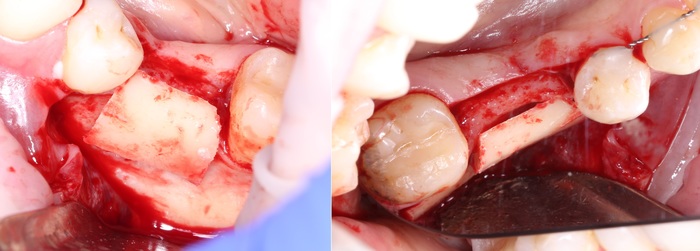

Размер блока должен соответствовать размерам области, которую необходимо восстановить (между зубами около 20мм.):

Примеряемся:

Примеряем наш блок: